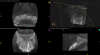

(9.) Preoperative radiograph of previously treated tooth No. 9, which received a diagnosis of acute apical abscess secondary to childhood trauma and recurrent endodontic pathology.

Figure 9

(10.) Posttreatment radiograph and cone-beam computed tomography (CBCT) scan following nonsurgical root canal re-treatment that resulted in incomplete resolution of symptoms in response to percussion and palpation.

Figure 10

(11.) Posttreatment radiograph and cone-beam computed tomography (CBCT) scan following nonsurgical root canal re-treatment that resulted in incomplete resolution of symptoms in response to percussion and palpation.